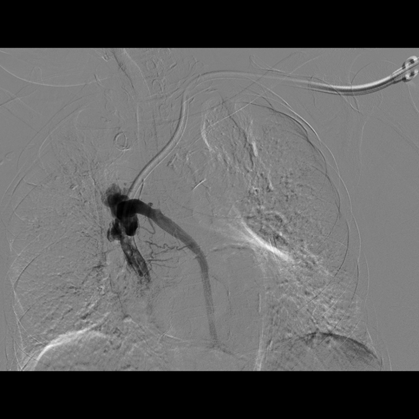

72岁钟阿姨,患尿毒症3年多,长期在我院维持性血液透析治疗,有糖尿病基础疾病,血管条件差,无法行动静脉内瘘手术建立血管通路。钟阿姨曾于2012年底在我院植入右侧颈内静脉半永久透析管,1年后因管路血流不通畅,予以行左侧颈内静脉半永久透析导管术,继续规律血液透析,近期因管路血流量不佳入我院住院治疗。入院后查CTV提示左侧颈内静脉纤细,上腔静脉怀疑血栓,右侧颈内静脉狭窄。由于考虑手术风险高,手术难度较大,肾内科严跃红主任医师邀请广州市第一人民医院放射介入科陈国东副主任医师,联合我院心血管介入科邓天明副主任医师和DSA室医护人员,术前全面评估,术中精细操作,血管造影显示:左侧锁骨下静脉、头臂静脉、上腔静脉上中段狭窄,上腔静脉下段完全闭塞,遂用三个球囊对狭窄闭塞的静脉血管进行逐级扩张成形后,上腔静脉血管复通,DSA引导下辅助半永久透析导管植入,手术成功。

血管闭塞